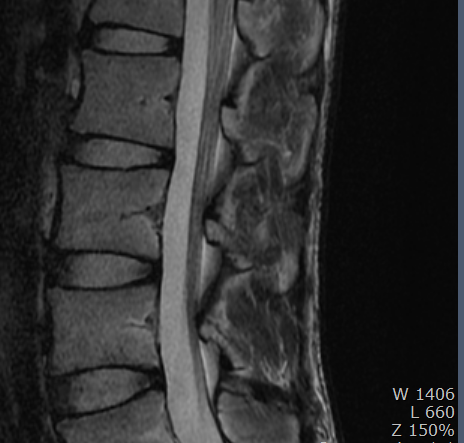

척추 mri를 찍어서 봤는데 저런식으로 홈이나 금간것저럼 보이는게 있는데 저건 뭔가요???

뼈에 금이 간게 아니라면 뭔지 궁금합니다

• 3번 째 사진

이런 경우에 골절이 아닌지 오해하시는 경우가 많은데 골절이 아닙니다.

골절의 경우에는 T1 영상에서 조영이 떨어지고 fat suppression T2 영상에서 조영이 증가하는 소견을 확인해야합니다.

골절이 아니면 왜 저렇게 보이는지 까지는 제가 잘 모르지만 저 소견을 이상소견으로 보이는 않습니다.